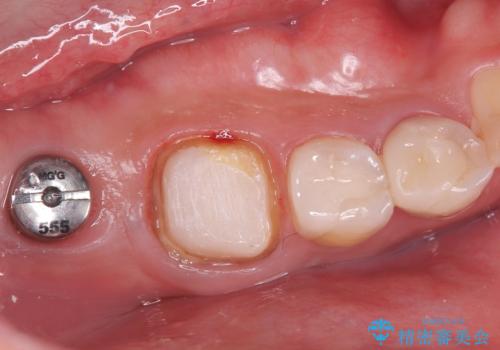

- 治療計画

- 患者様は、右側の奥歯でしっかり噛めないことを主訴に来院されました。診察の結果、右上6・右下6の根管治療が不十分で、感染のリスクがある状態と判断。これらの歯は再根管治療を行い、セラミッククラウンで補綴することにしました。また、右上7・右下7は欠損しており、噛み合わせを回復するためにインプラント治療を計画しました。

まず、右上6・右下6の根管治療を再度行い、根の状態をしっかり整えた上で、セラミッククラウンを装着しました。さらに、欠損していた右上7・右下7にはインプラントを埋入し、セラミッククラウンを装着。治療後は、「奥歯でしっかり噛めるようになり、不安なく食事ができるようになった」と患者様にも大変ご満足いただきました。